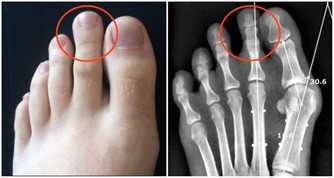

根據醫學專家的說法,眼睛的輕微發黃可能表明這個情況。眼抽搐和眼瞼痙攣也是有助於查明維生素B12缺乏症的跡象。在極少數情況下,可能導致視力喪失的視神經損傷可能發生。